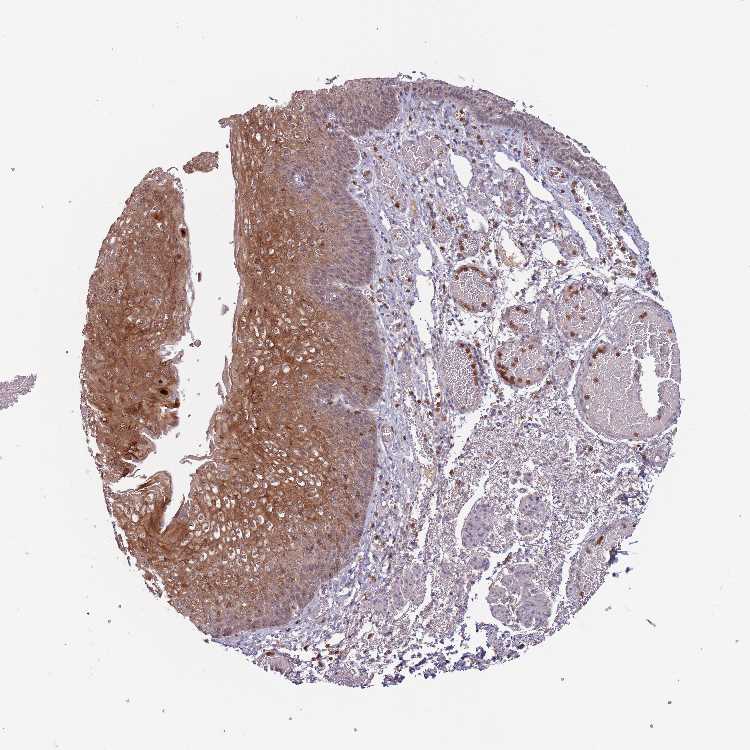

ESOPHAGUS - Antibody stainingi

Antibody staining in the annotated cell types in the current human tissue is reported as not detected, low, medium, or high, based on conventional immunohistochemistry profiling in selected tissues. This score is based on the combination of the staining intensity and fraction of stained cells.

Each image is clickable and will lead to virtual microscopy that enables deeper exploration of all samples and also displays staining intensity scores, fraction scores and subcellular localization as well as patient and tissue information for each sample.

Antibody HPA015535Antibody HPA043136Antibody HPA047029Antibody HPA047052

Squamous epithelial cells Not detectedMediumNot detectedNot detected